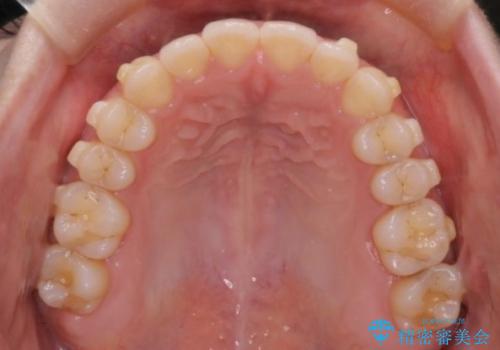

- 前歯の凸凹を主訴に来院された患者様です

骨格性の下顎前突傾向もあったため、臼歯関係の遠心移動も行うことで綺麗な仕上がりで矯正を終了することができました。

遠心移動を行うことで期間はかかりましたが、良い状態で仕上がっています。